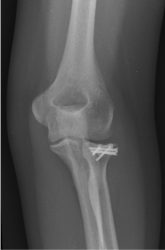

1b. X-rays after surgery, showing the fracture after fixation

A rotation of the x-ray